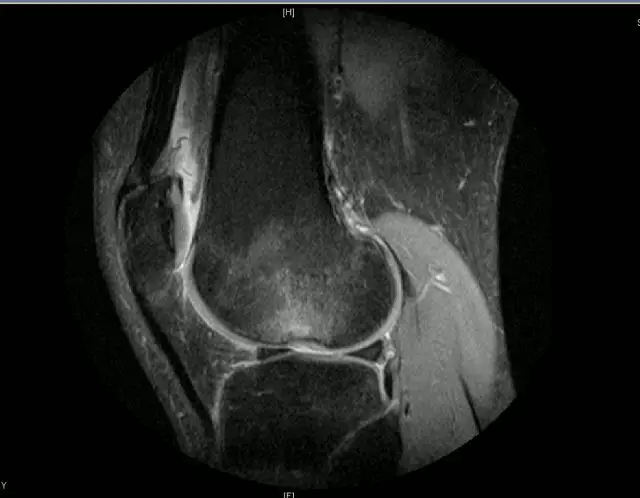

关节扭伤常常导致膝关节相关韧带结构的损伤,如何及时发现这些损伤并进行相关的治疗,是我们临床医师常常面临的问题,除了相关病史、临床体征之外,磁共振扫描也是重要的诊断依据

膝关节的解剖结构

正常的膝关节

韧带结构:形态,张力,质地,连续性

半月板:完整性,形态,质地

Blumensaat 角(-1.6度)

大于9-15度视为异常

前交叉韧带与胫骨平台角度(56度)

小于45-50度视为异常

后交叉韧带折弯度

弧度:0.19厘米,角度:114-123度